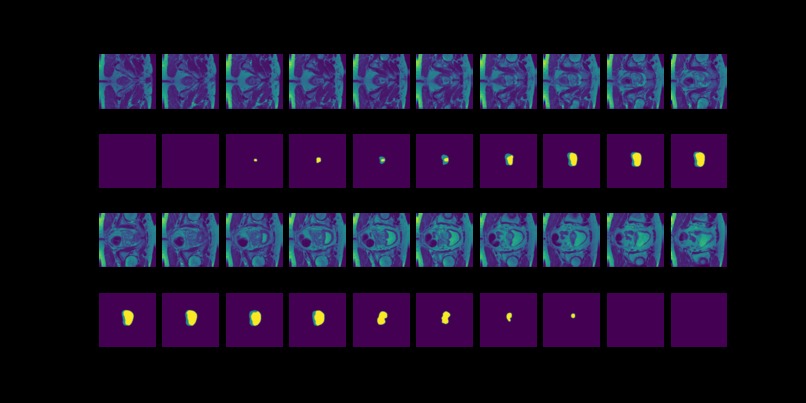

Figure 3: MRI slices (first and thrid rows) from one study with labels (second and fourth rows).

The prostate data set was acquired at Radboud University Medical Center, Nijmegen Medical Centre, Nijmegen, The Netherlands. It consists of 48 prostate multiparametric MRI (mpMRI) studies, 32 of them have corresponding region-of-interest (ROI) targets (background= 0, TZ= 1 and PZ= 2). Each study contains approximately 15 to 20 slices of MRI images, resulting in 602 images in total. Figure 3 shows the 20 slices from one study. The first and last few MRI slices contain little segmentation information. Therefore, to simplify the problem, we will discard the first and last 5 MRI slices from each study. We will use 10 studies (95 images) as the test set and the remaining 22 studies (187 images) as the training set.